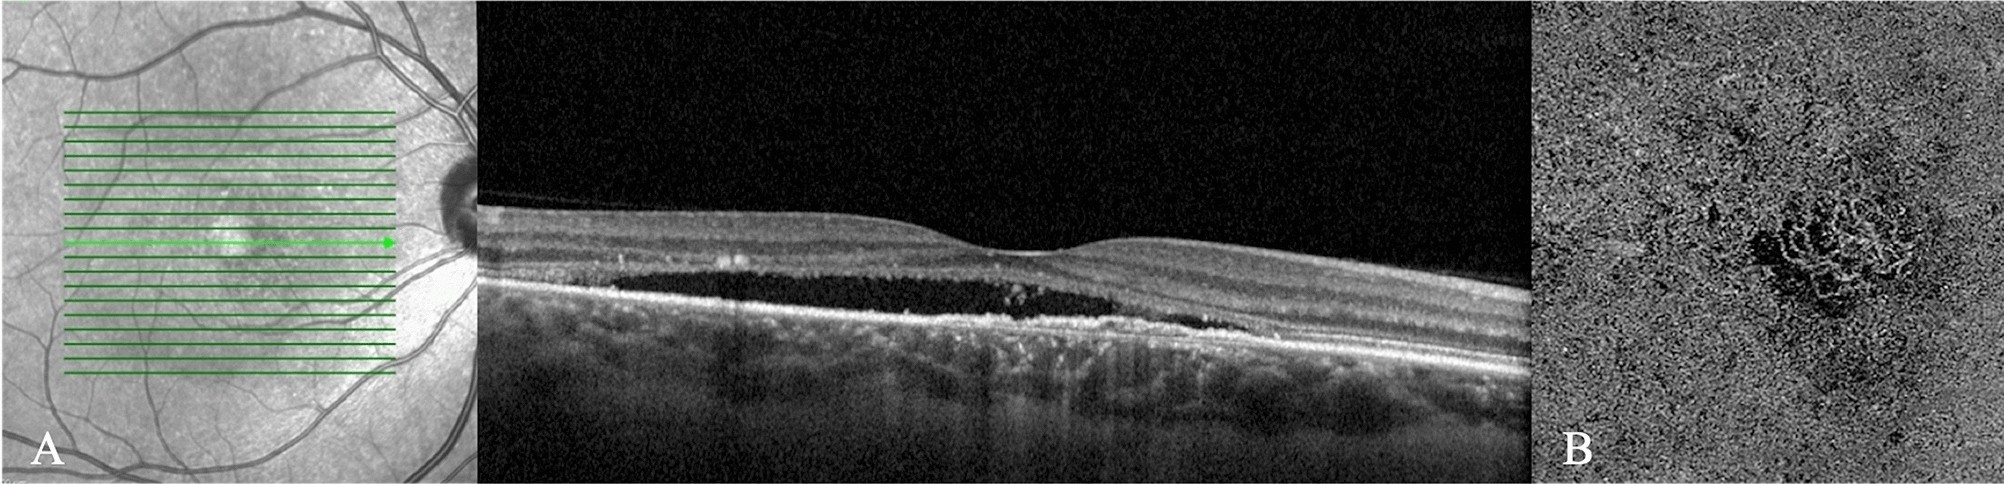

Figure 2

(A) Enhanced-depth imaging optical coherence tomography reveals dilated Haller’s layer vessels and attenuation of the choriocapillaris, and a flat irregular pigment epithelium detachment (FIPED) associated with subretinal fluid (SRF) and subretinal hyperreflective foci. (B) The enface OCT angiography demonstrates a neovascular lesion with tangled filamentous pattern within the FIPED.